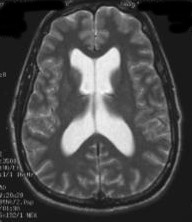

In May 2008, the patient was taken back to surgery and the OSV-2 was placed. The following 4 Valve DiaCeph Graph depicts his performance with 4 past valves, including the recent OSV-2, and when his Medos valve reset upwards. The patient reported much improved complaints after discharge. Here is a Comparative DiaCeph Graph 3 months post. The real proof came in the 6 month follow-up CT scan below - far right - normal sized ventricles. His scans demonstrated ventricular dilatation like the two images at left, and even larger, during the 16 years he was shunted.

Dec 2003 OSV-1 c/o         June 2007 OSV-1 preRevision          Nov 2007 Medos w SG                         Oct 2008 OSV-2